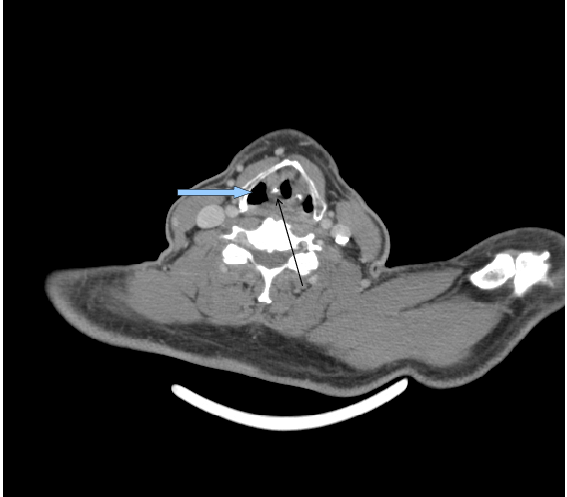

What structure is the blue arrow pointing to

Thyroid